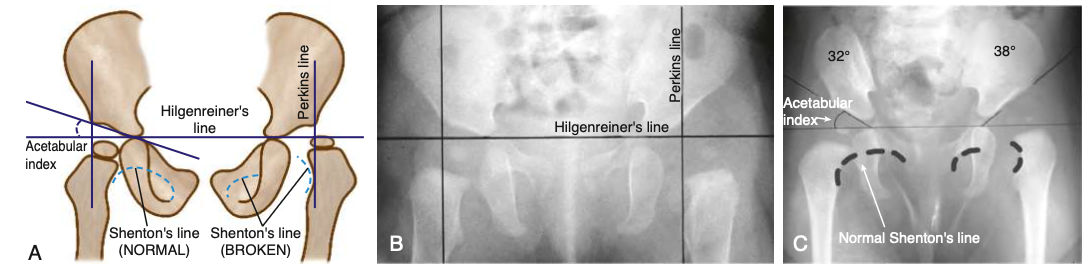

• 고관절 엑스레이 (생후 5~6개월 후부터 가능)

→ 대퇴 골두가 Hilgenreiner선보다 상방으로, Perkins 선보다 외측으로 전위